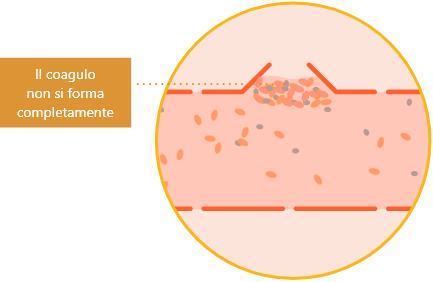

In presenza di emofilia, con un fattore della coagulazione mancante o a bassi livelli, il processo della coagulazione non può svolgersi correttamente.

Il coagulo non riesce a formarsi in modo stabile nel sito della lesione e, di conseguenza, continua il sanguinamento nei tessuti.